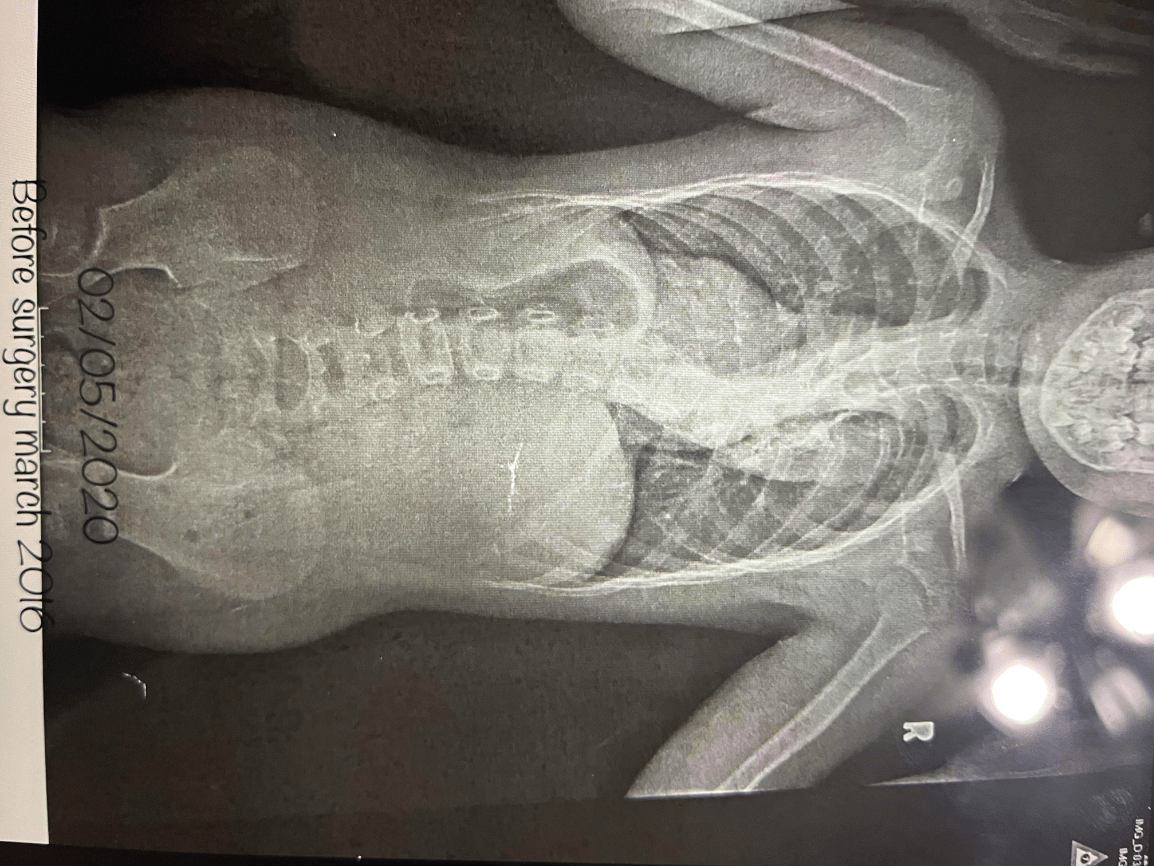

Scoliosis

1)Complete/Incomplete? 2)Displaced/Nondisplaced?

3)Open/Closed? 4)What type of Fracture?

5)What Bone?

1)Complete

2)Displaced

3)Closed

4)Avulsion

5)Humerus